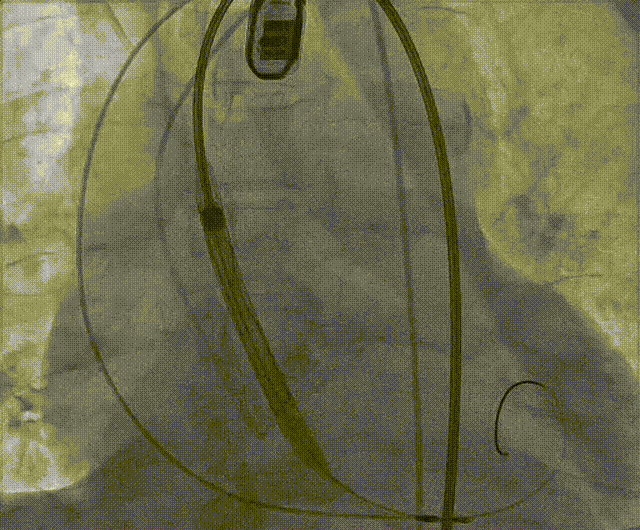

手术流程概括

根部造影

左冠脉提前植入延长导管,预埋冠脉导丝。

20mm球囊预扩张,无腰征,无造影剂泄露。

vitaflow tav24瓣膜轻松过弓初始定位瓣环0位开始释放,班第一次释放瓣膜在转移到瓣上,综合决定回收采取第二次瓣膜释放。

第二次精准零位释放,决定完全释放。

释放后多体位观察造影,瓣膜位置良好,展开良好,轻微瓣周漏。